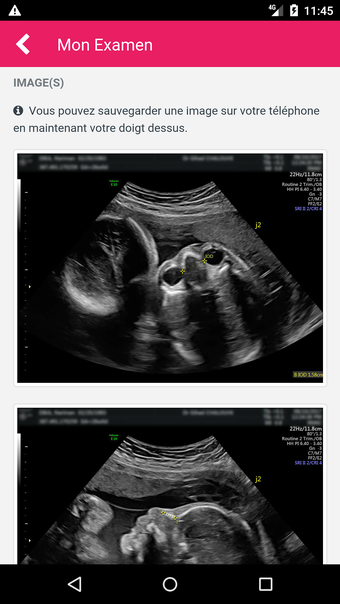

MediFile is an application for medical professionals to manage all of their ultrasound images, reports, and other patient data in one place. The application allows them to scan, view, and save their files directly from their device. The application has the capability to upload reports to the server of the doctor or midwife, for whom the report was sent.

The main advantage of the application is that it makes it very easy for the medical professional to view and share their patient's data with their colleagues. It also facilitates the creation of a patient database and a communication channel for all of the medical professionals working on the same case.